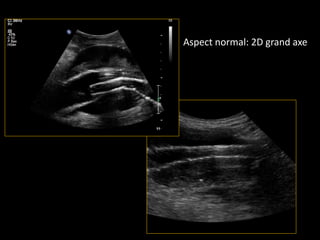

Aspect normal: 2D grand axe

• Réduction de calibre du sac ++++ (mode 2D)

• Aspect du thrombus (2D)